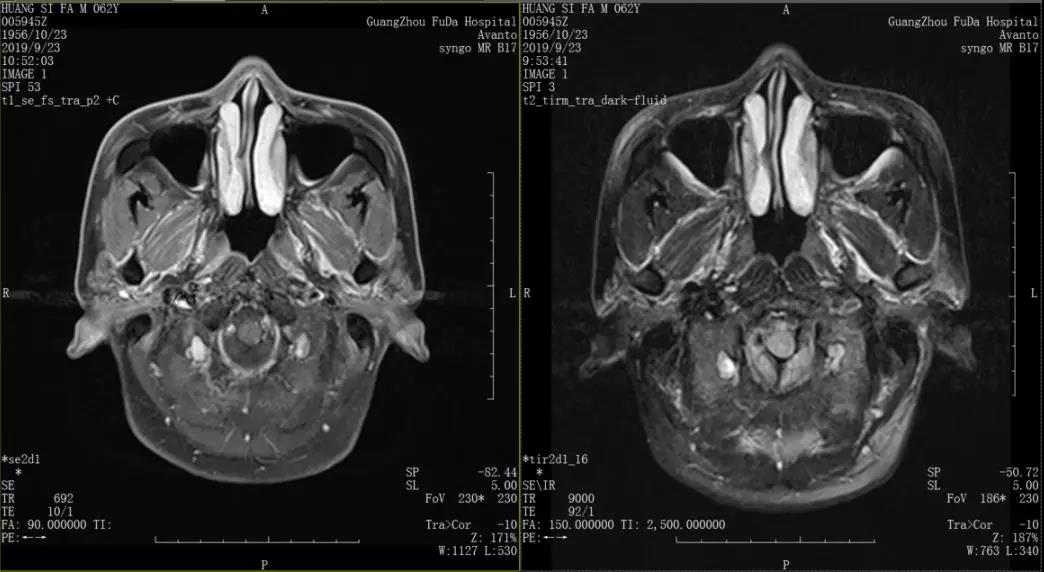

住院期间,黄先生通过全身检查和拍CT等项目后,诊断结果报告书写着“鼻咽部未分化型非角化癌 T3N1M0 III期、右侧结节性甲状腺肿、胆囊结石、右肾囊肿、右肾结石、前列腺小钙化灶。”这让硬汉父亲顿时有点慌张,他抓着一旁的儿子手久久不可松开。“我以前觉得我父亲还是我印象中那个硬汉,在此时我才觉发现原来他也有脆弱的时候。”黄叔叔的儿子回忆道。